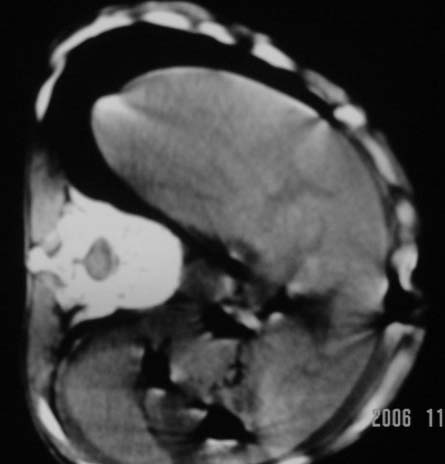

仰卧位见:肝前间隙及肝脾间隙内可见新月形气体密度影,边缘清楚,侧卧位见气体随体位改变而移动,ct值约-929hu。膈下、肝下间隙及部分肠间隙可见液性密度影。考虑:1、上腹部空腔脏器穿孔,以胃穿孔可能性大。2、少量腹水。

仰卧位见:肝前间隙及肝脾间隙内可见新月形气体密度影,边缘清楚,侧卧位见气体随体位改变而移动,ct值约-929hu。膈下、肝下间隙及部分肠间隙可见液性密度影。考虑:1、上腹部空腔脏器穿孔,结合临床,首先考虑胃穿孔可能性大。2、少量腹水

肝前间隙及肝脾间隙内可见新月形气体密度影,边缘清楚,侧卧位见气体随体位改变而移动,

补充--肝门及肝肾间隙以见积气显示。

支持消化道空腔脏器穿孔(腹腔内大量游离气体影,小网膜囊内亦见气体影),少量腹水。